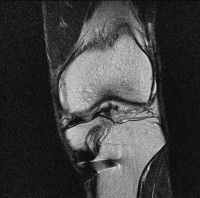

무릎 mri 간단히 봐주실 수 있으시나요 ㅠㅠ

안녕하세요 8년전 십자인대 수술하고 최근 무리한 운동에 무릎 불편감이 생겨서

mri 찍었습니다.

진단결과는 첫 찍은 병원에서 활액막염 이라는 진단을 받았습니다. 혹시 봐주실 수 있으실까요?

올라온 MRI가 단편적이라서 정확한 진단에 어려움이 있지만 십자인대에는 큰 이상이 있지는 않은것 같으며, 무릎관절내 물이 있는 것으로 보아 활액막염의 진단이 맞을 것 같습니다.

하지만 단편적인 영상이기 때문에 촬영병원에서 정확한 판독지 등을 받으시는 것이 좋겠습니다.